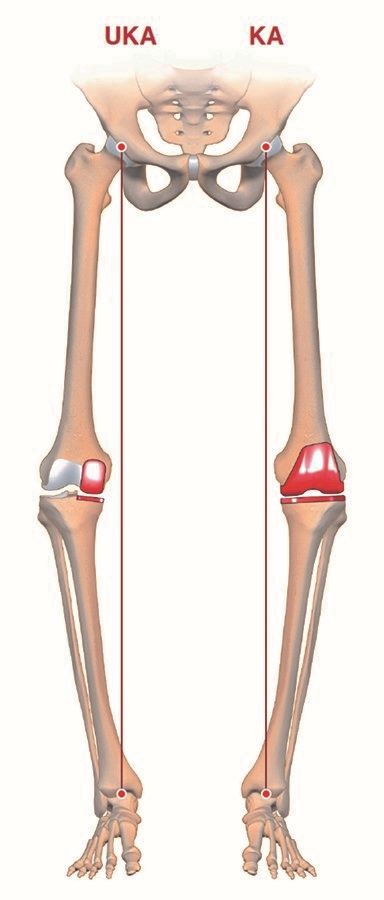

However, the disappointing outcome with up to 20 % unsatisfied patients after MA TKA and a better understanding of knee biomechanics have prompted discussion into alternative alignment concepts that give more respect to the patient’s constitutional anatomy. There is an ongoing controversy, which alignment concept is the best for our TKA patients. At least five different “philosophies” are currently under debate (Figure 1) (1). So far there is no evidence that one of them might be in favour for a better functional outcome, can reduce the 20% unsatisfied patients or achieve better long-term survival. This article presents the various schools of thought and their potential advantages and disadvantages.

KA: Kinematic alignment, rKA: restricted kinematic alignment, aMA: adjusted mechanical alignment,

MA: mechanical alignment, AA: anatomic alignment.